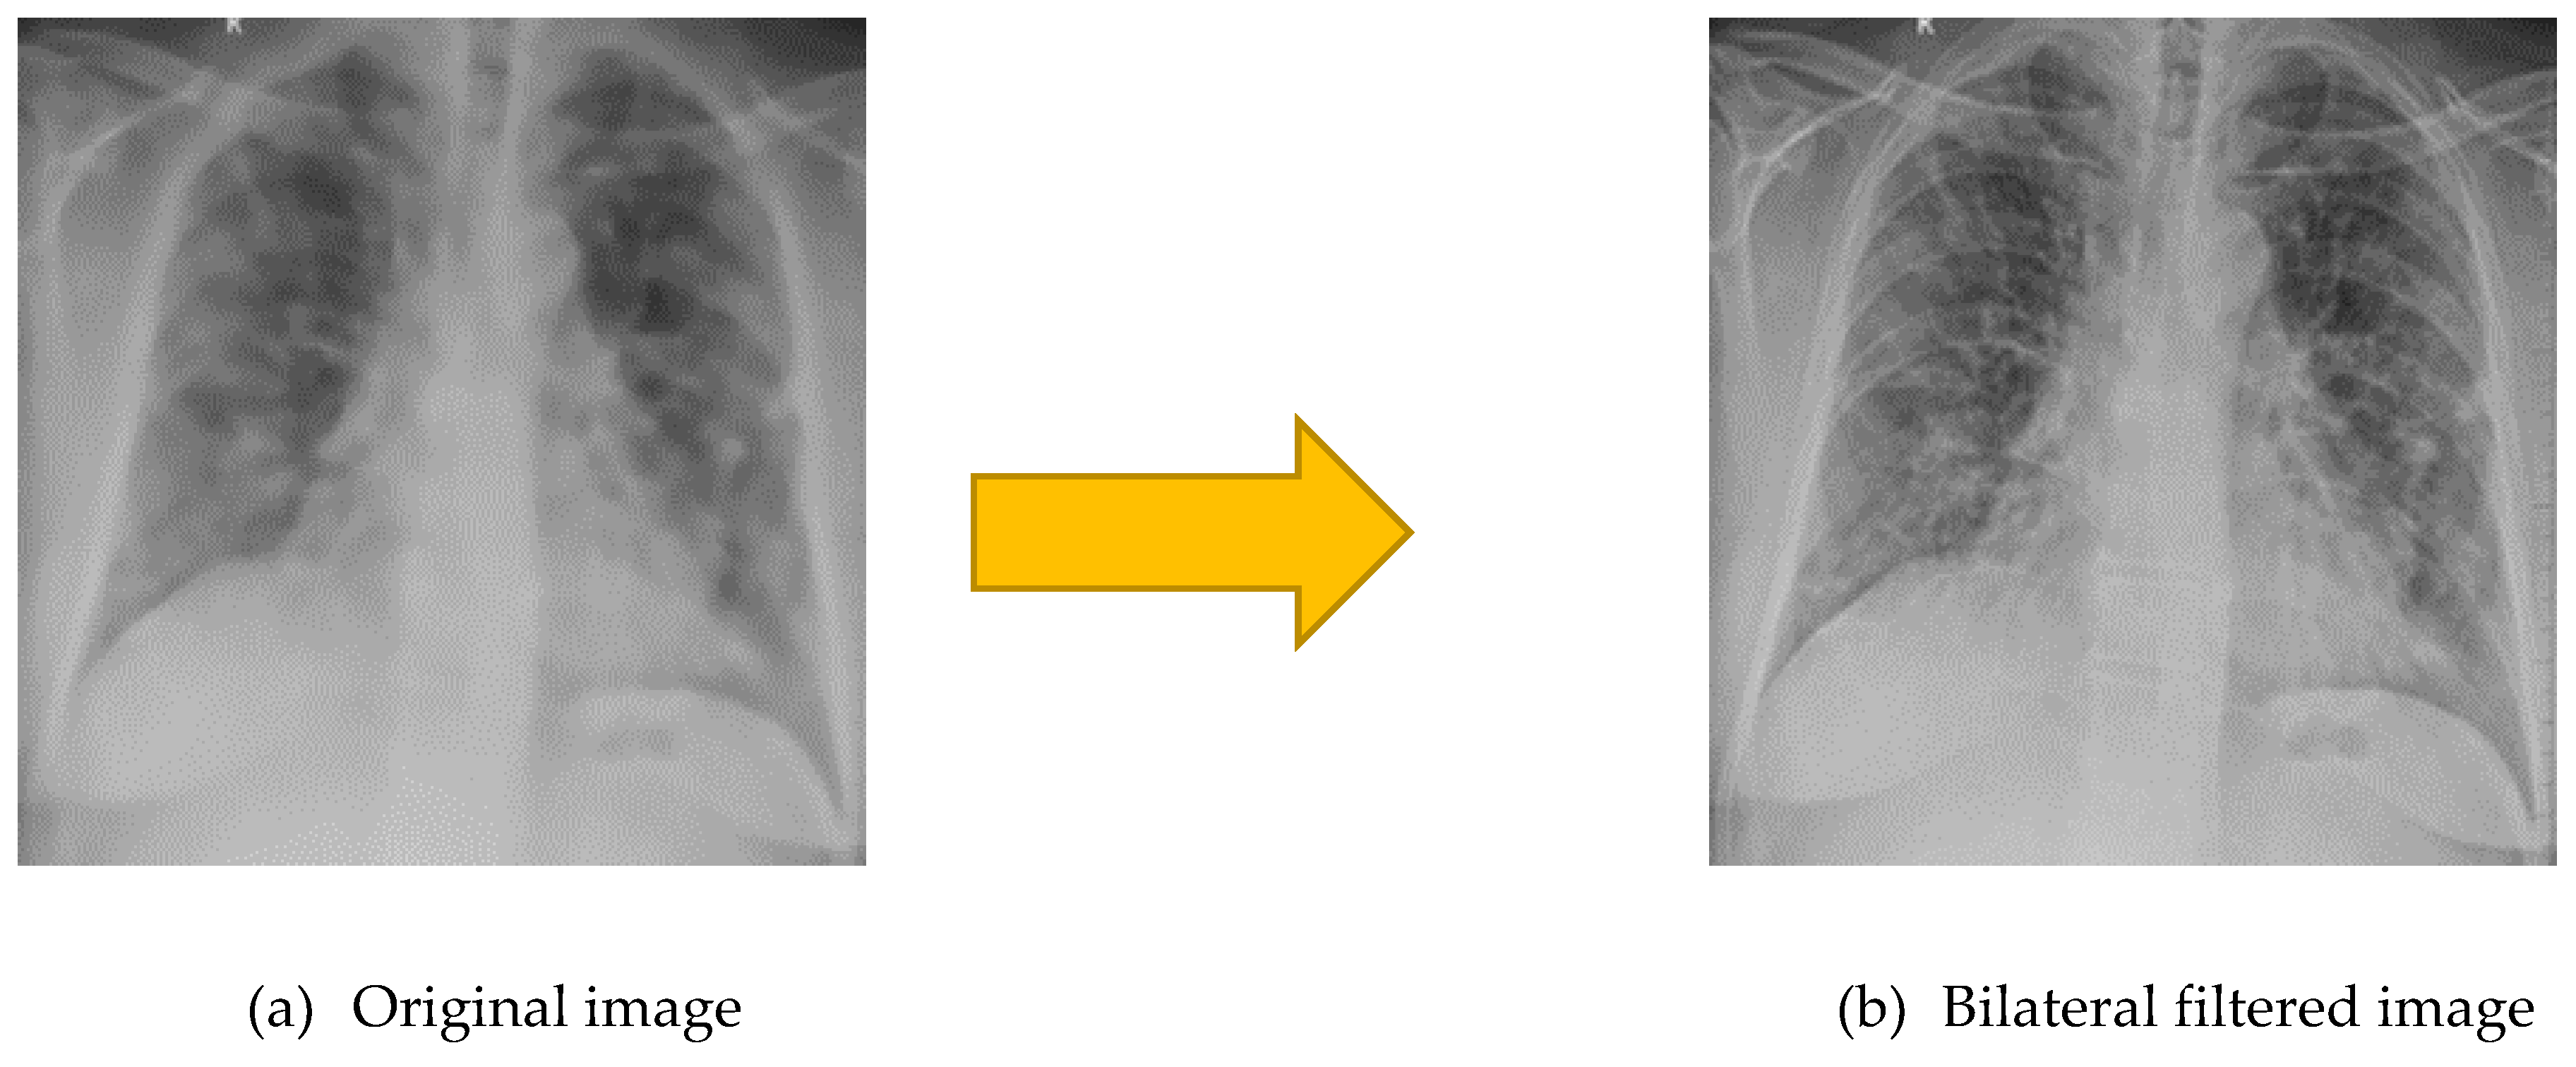

2.2.4. Bilateral Filtering

| Parameter | Effect | Selected Value |

|---|---|---|

| D | Diameter of the pixel neighborhood. Larger values mean a stronger effect. | 9 |

| sigmaColor | Color differences affect filtering; a larger value means more smoothing. | 75 |

| sigmaSpace | How far in space does the filter look? Larger value considers more distant pixels. | 75 |